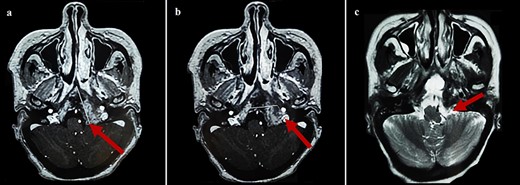

By the end of biological exploration, the patient reported a recurrence of headaches and blurred vision, 2 months after surgical decompression. Cerebral MRI revealed a relapse of the sphenoid plasmacytoma, measuring 70 mm (Fig. 3). Given the pathological diagnostic result, surgical re-intervention was not decided. Instead, the patient was treated with external beam radiotherapy (RTX) focused on the sphenoid bone (30 Gy), followed by immunochemotherapy with zoledronic acid. After 6 months, complete response was noted with the resolution of symptoms, disappearance of the monoclonal band, normalization of sFLC, and persistence of lytic sequelae on cerebral MRI (Fig. 4). Autologous stem cell transplantation (ASCT) was successfully performed, and the patient was put under treatment maintenance. After 18 months of follow-up, clinical, biological, and radiological evaluation confirmed sustained complete remission.

Control cerebral MRI (axial views) showing the disappearance of the sphenoid BP after treatment with RTX and immunochemotherapy. (a: T1-weighted; b: T2-weighted).